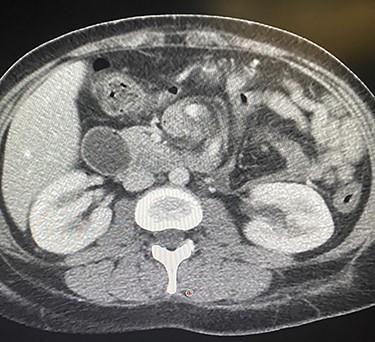

A 35-years-old female, 9 months post-endoscopic gastroplasty presented to the emergency department complaining of epigastric abdominal pain for 5 days, the pain is radiating to the umbilicus associated with nausea and vomiting. On general examination, she is vitally stable with HR 88 B/min, BP 116/66 and temperature 36.9°C, the abdominal examination showed epigastric and tenderness. On abdomen CAT scan, she had partial small bowel obstruction with adhesive band originating from the stomach (Fig. 1). Barium meal showed dilatation of the second part of duodenum due to band like structure (Fig. 2). The patient admitted to the hospital with a diagnosis of small bowel obstruction and kept NPO; Nil Per Os, on IV fluids and nasogastric tube drainage.

CAT scan showing partial small bowel obstruction with adhesive band originating from the stomach.